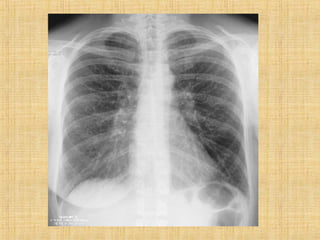

As principais informações do documento são: 1. Discute os padrões de doença pulmonar causados por metástases, incluindo nódulos, espessamento intersticial e obstrução das vias aéreas. 2. A prevalência de metástases pulmonares varia de 30-55% dependendo do tumor primário, e são mais comuns em pacientes acima de 50 anos. 3. Os achados clínicos mais comuns são dispneia, hemoptise e febre, enquanto exames de escarro ou lavado brô